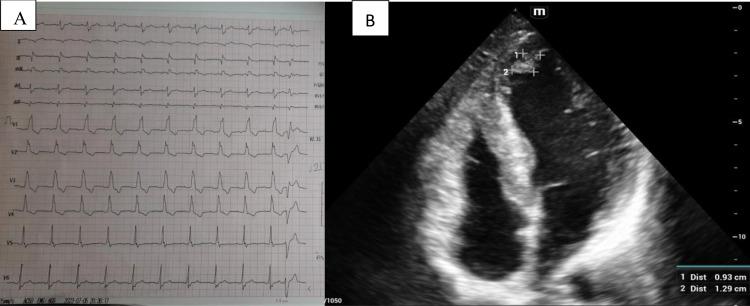

New oral anticoagulants (NOACs) have become more popular in the last few decades. Although apixaban has been proven to be safer than warfarin and causes less hemorrhage in comparison to other NOACs, it still poses a risk of spontaneous bleeding. We present here an 81-year-old male known case of heart failure with reduced ejection fraction (HFrEF) associated with an apical thrombus of 0.93×1.29 cm who presents with cognitive decline, slurred speech, and right side weakness following apixaban use for his apical thrombus. On further evaluation of non-contrast brain (), there was a large extra-axial subacute subdural hematoma with thick septations in the left parietal region, measuring 2.6 cm in thickness, causing an a mass effect, and an a midline shift of 1 mm. Following neurosurgery, cardiology, and anesthesiology discussions, the surgery was deferred due to his age and coexisting conditions with regular follow-ups. The patient has now gained full consciousness and is currently undergoing physiotherapy. This case highlights an elderly patient with apixaban-induced subdural hemorrhage, which is a rare entity in the medical literature. Although apixaban is safer than other NOACs, it may cause subdural hemorrhage.

在过去几十年中,新型口服抗凝剂(NOACs)越来越受欢迎。尽管已证实阿哌沙班比华法林更安全,与其他NOACs相比出血更少,但它仍有自发性出血的风险。我们在此介绍一名81岁男性,已知患有射血分数降低的心力衰竭(HFrEF),伴有0.93×1.29 cm的心尖血栓,在使用阿哌沙班治疗心尖血栓后出现认知衰退、言语不清和右侧肢体无力。在进一步评估非增强脑部()时,左顶叶区域有一个巨大的轴外亚急性硬膜下血肿,有厚分隔,厚度为2.6 cm,产生占位效应,中线移位1 mm。经过神经外科、心脏病学和麻醉学讨论后,由于患者年龄和并存疾病,手术延期,并定期进行随访。患者现已完全清醒,目前正在接受物理治疗。该病例突出了一名老年患者发生阿哌沙班诱导的硬膜下出血,这在医学文献中是一种罕见的情况。尽管阿哌沙班比其他NOACs更安全,但它可能导致硬膜下出血。